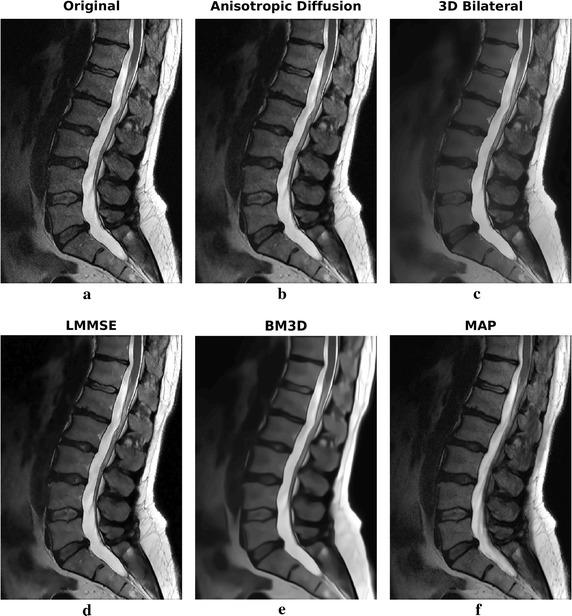

The method exploits Markov random fields in order to implement a 3D maximum a posteriori estimator of the image. Due to the local nature of the considered model, the algorithm is able do adapt the smoothing intensity to the local characteristics of the images by analyzing the 3D neighborhood of each voxel. The effect is a combination of details preservation and noise reduction. The algorithm has been compared to other widely adopted denoising methodologies in MRI. Both simulated and real datasets have been considered for validation. Real datasets have been acquired at 1.5 and 3 T. The methodology is able to provide interesting results both in terms of noise reduction and edge preservation without any supervision.

该方法利用马尔可夫随机场来实现图像的三维最大后验估计器。由于所考虑模型的局部性质,该算法能够通过分析每个体素的三维邻域,使平滑强度适应图像的局部特征。效果是细节保留和降噪的结合。该算法已与MRI中其他广泛采用的去噪方法进行了比较。模拟数据集和真实数据集均已用于验证。真实数据集是在1.5T和3T下采集的。该方法能够在无需任何监督的情况下,在降噪和边缘保留方面提供有趣的结果。